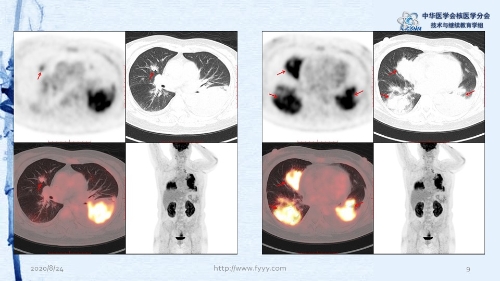

病例82:肉芽肿性血管炎PET-CT显像一例-【CSNM继教学组】郑山 福建医科大学附属第一医院